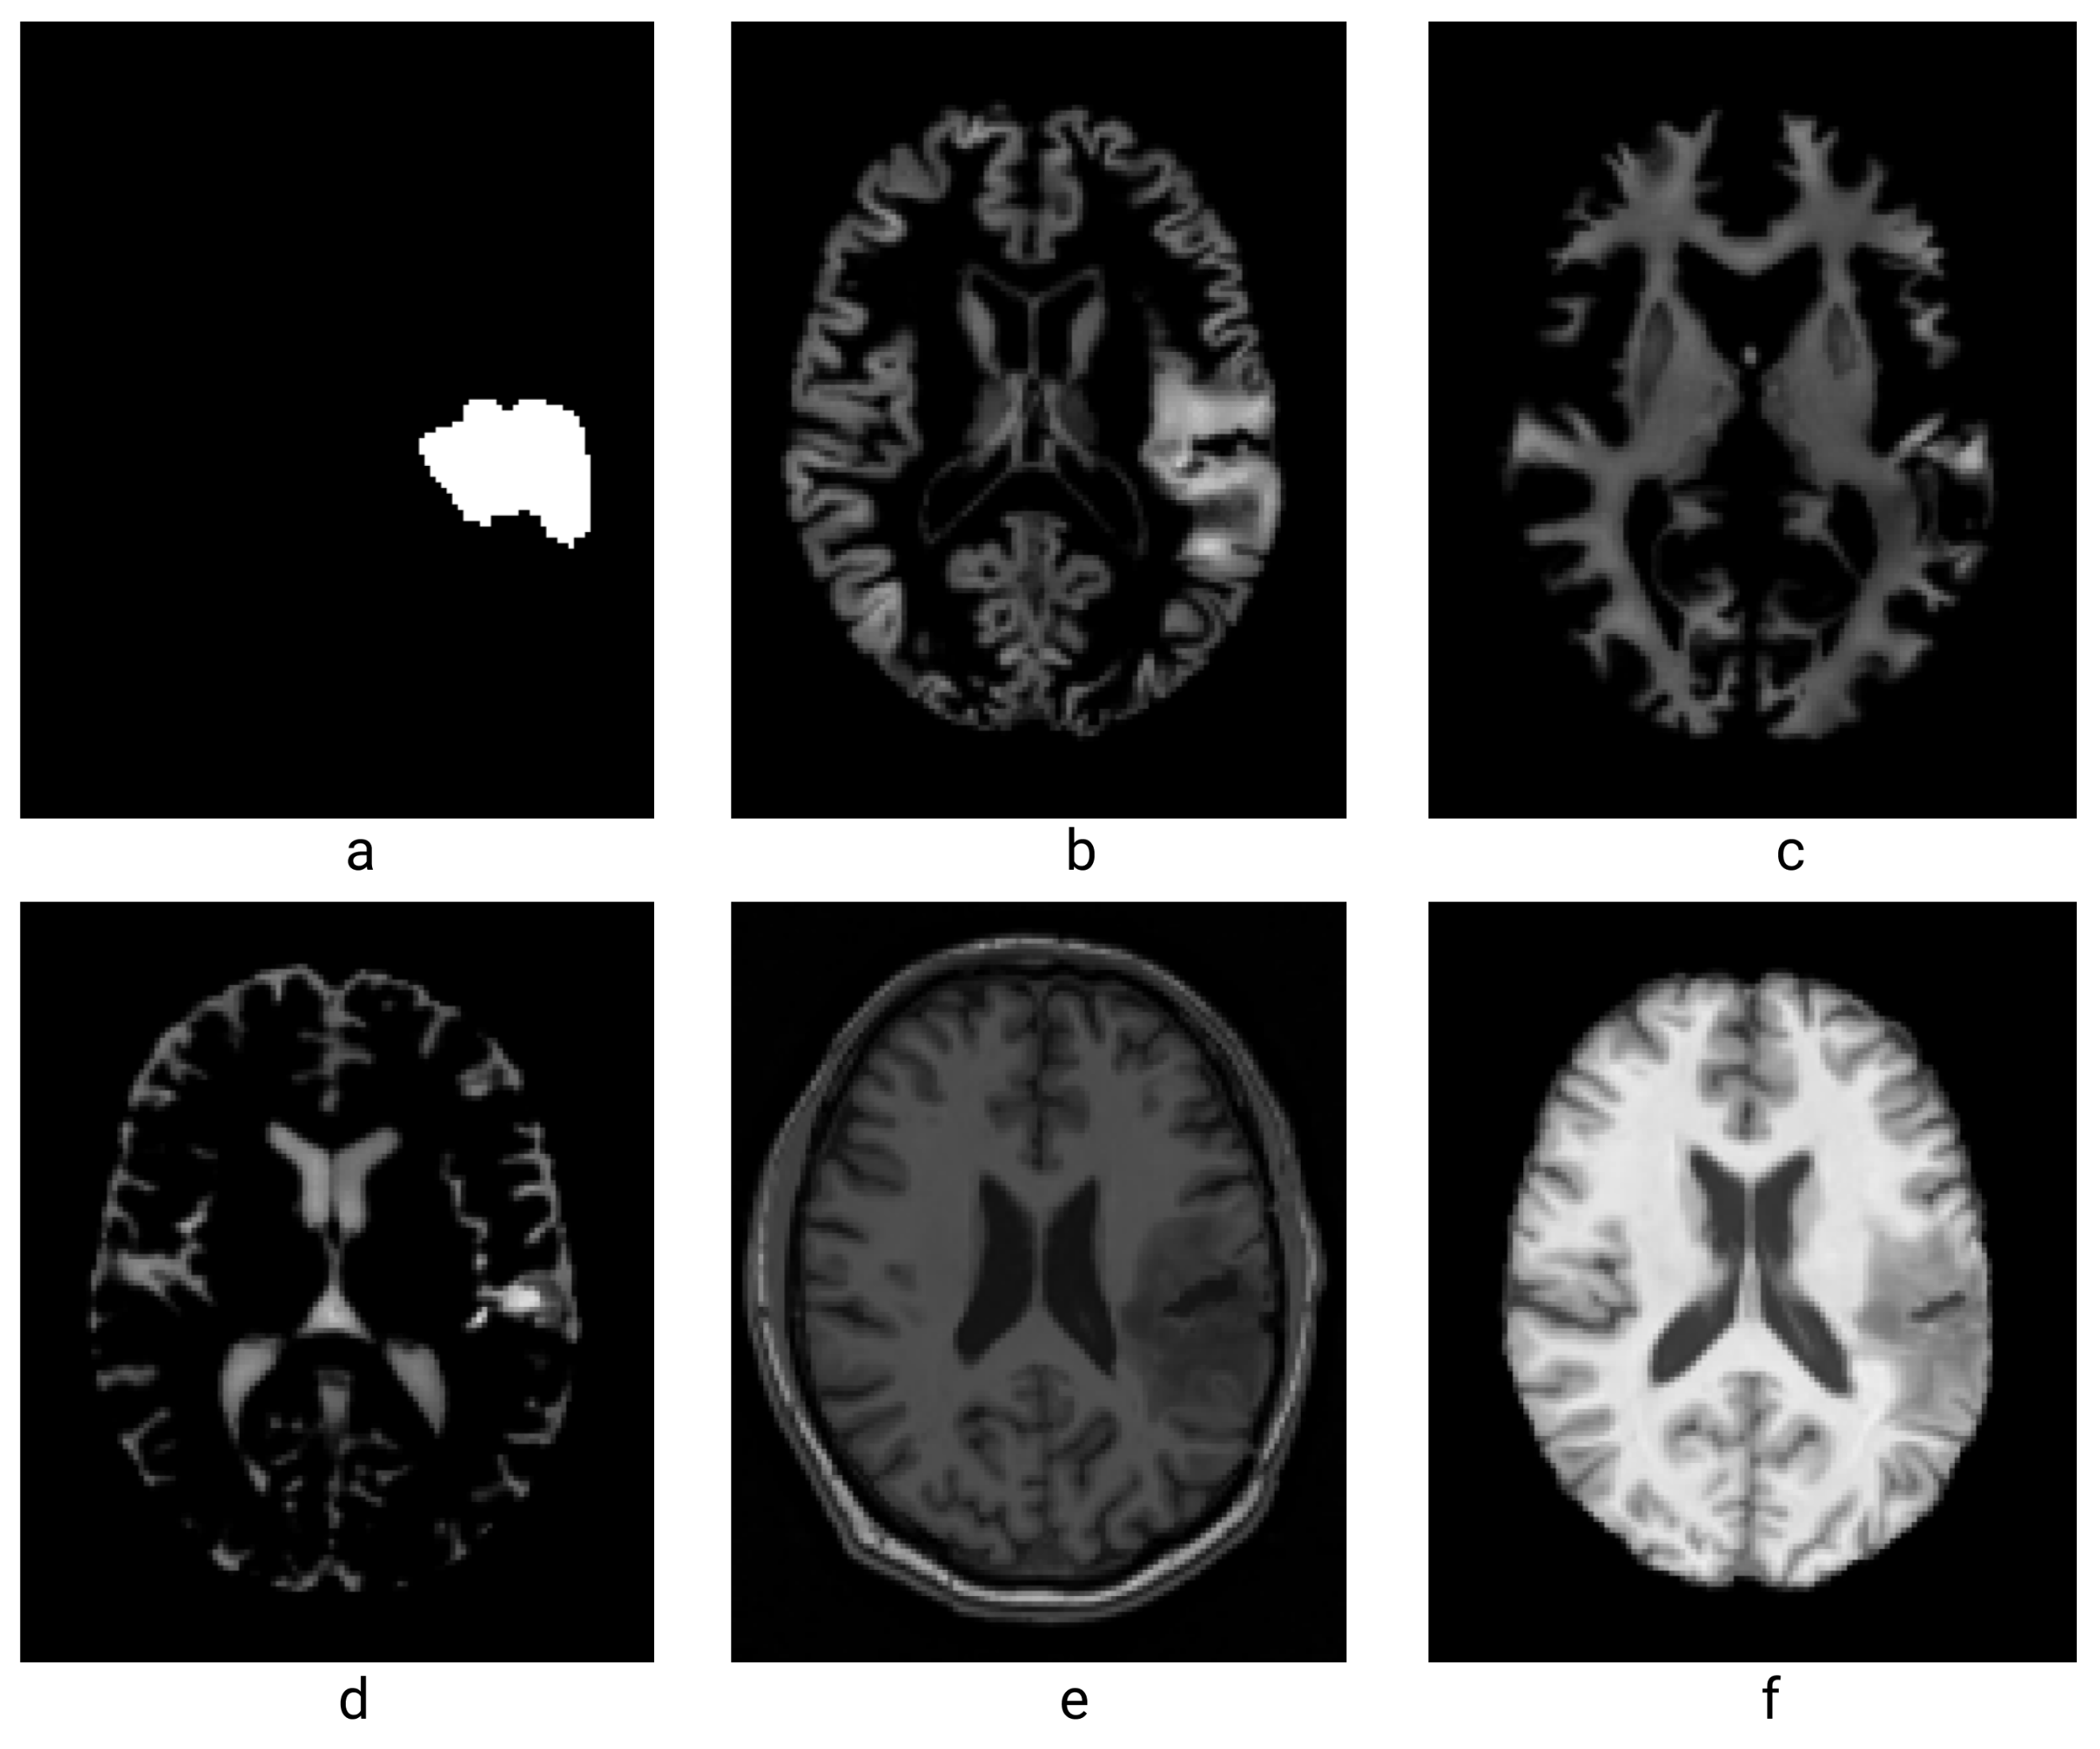

| Unhealthy Patient Image Data Description | ||

|---|---|---|

| Files Provided | Description | |

| 1 | Lesion.nii | This file is the binary mask for the brain tumor, each corresponds to a patients |

| 2 | Grey Matter mask (mrwp1) | Is the mask for the gray matter (useful since the activation are all in the gray matter) |

| 3 | White Matter mask (mrwp2) | Is the mask for the white matter (no activation inside the white matter, but may be a good way to estimate the brain deformations linked to the tumor and the peritumoral edema) |

| 4 | Cerebrospinal fluid mask (mrwp3) | The mask for the cerebrospinal fluid (like for the white matter, no activation inside, but may be useful to estimate brain deformations) |

| 5 | Whole brain–white gray matter (wms) | The whole brain (white and gray matter) in T1 anatomical MRI sequence, with the skin and skull clipped |

| 6 | Whole brain (wmrs) | This provides view of the whole brain cerebrospinal fluid, skull and skin included |